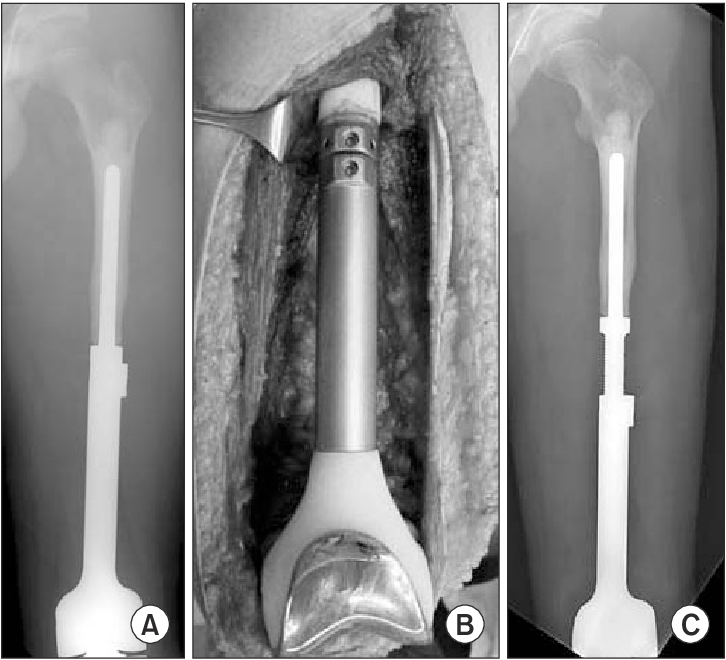

LIMB LENGTH DISCREPANCY 는 Malignant tumor resection 시에도 적용될 수 있는데 2cm 이내라면 추가적인 치료가 필요하지 않지만 2~5cm 의 경우 epiphysiodesis 가 필요하며, 5cm 이상 LLD 가 날 경우 rotationplasty, limb lengthening expendable prosthesis, staged lengthening 등을 시행할 수 있습니다.